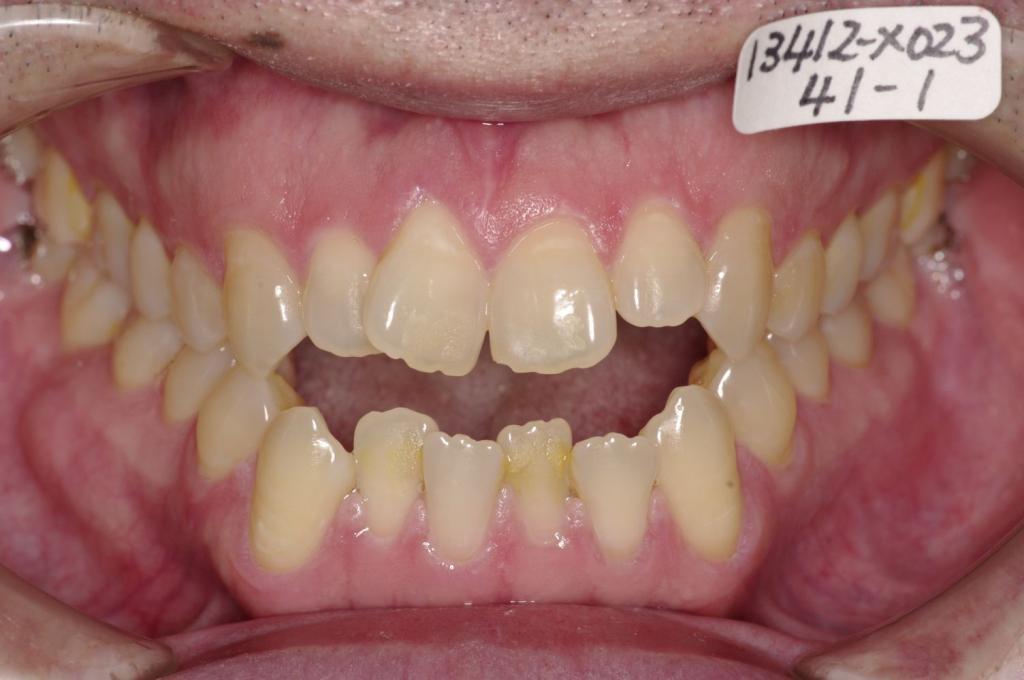

顎、顔の歪みの矯正治療

(治療期間、治療前後写真、治療方法、費用)WORKS